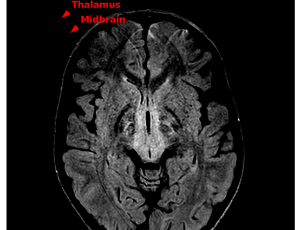

Progressive ophthalmoplegia, cyclical hypersomnolence, and sensorineural hearing loss in a child with genetically confirmed Kearns-Sayre Syndrome: A diagnostic odyssey

Background: Kearns-Sayre syndrome (KSS) is a rare mitochondrial DNA deletion disorder presenting before the age of 20 years, characterized by progressive external ophthalmoplegia, pigmentary retinopathy, and systemic manifestations including cardiac, endocrine, and neurological features. Early recognition remains challenging due to its heterogeneous and evolving phenotype.